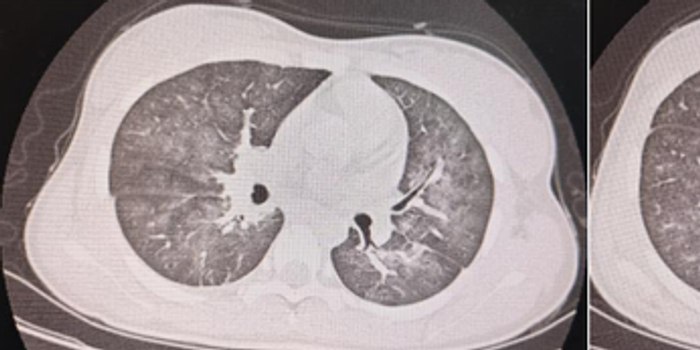

不久前,一名重症肺炎患儿自外院转诊至齐鲁医院德州医院小儿科,来院时出现了呼吸困难、低氧症状危急的情况,但其胸部CT却显示,炎症面积并未达到危重程度。

面对患儿症状与影像学表现的反差异常,团队凭借丰富的临床经验判断,气道内大概率暗藏梗阻。紧急实施支气管镜检查后,发现患儿气道内大量分泌物重度壅堵,这便是引发呼吸危象的“隐形元凶”。医护团队当即开展镜下灌洗精准操作,快速打通呼吸通道,患儿缺氧症状即刻缓解,后经针对性抗炎治疗,患儿逐步痊愈。

反差迷局:精准狙击特殊致病菌

相较于上一例重症肺炎患者,患儿茜茜(化名)的病情更具迷惑性。她的胸部CT提示,肺部炎症范围广泛,但茜茜却没有明显呼吸困难的表现,支气管镜检查也未发现显著阻塞或病变,那么胸部CT表现又是怎么回事呢?

小儿科呼吸亚专业团队并未被表象迷惑,而是结合详细的化验结果深挖病因,最终锁定“特殊致病菌感染”这一核心症结,并针对性制定靶向抗感染治疗方案,精准用药后,茜茜肺部的炎症逐步消退,病情得到了明显好转。